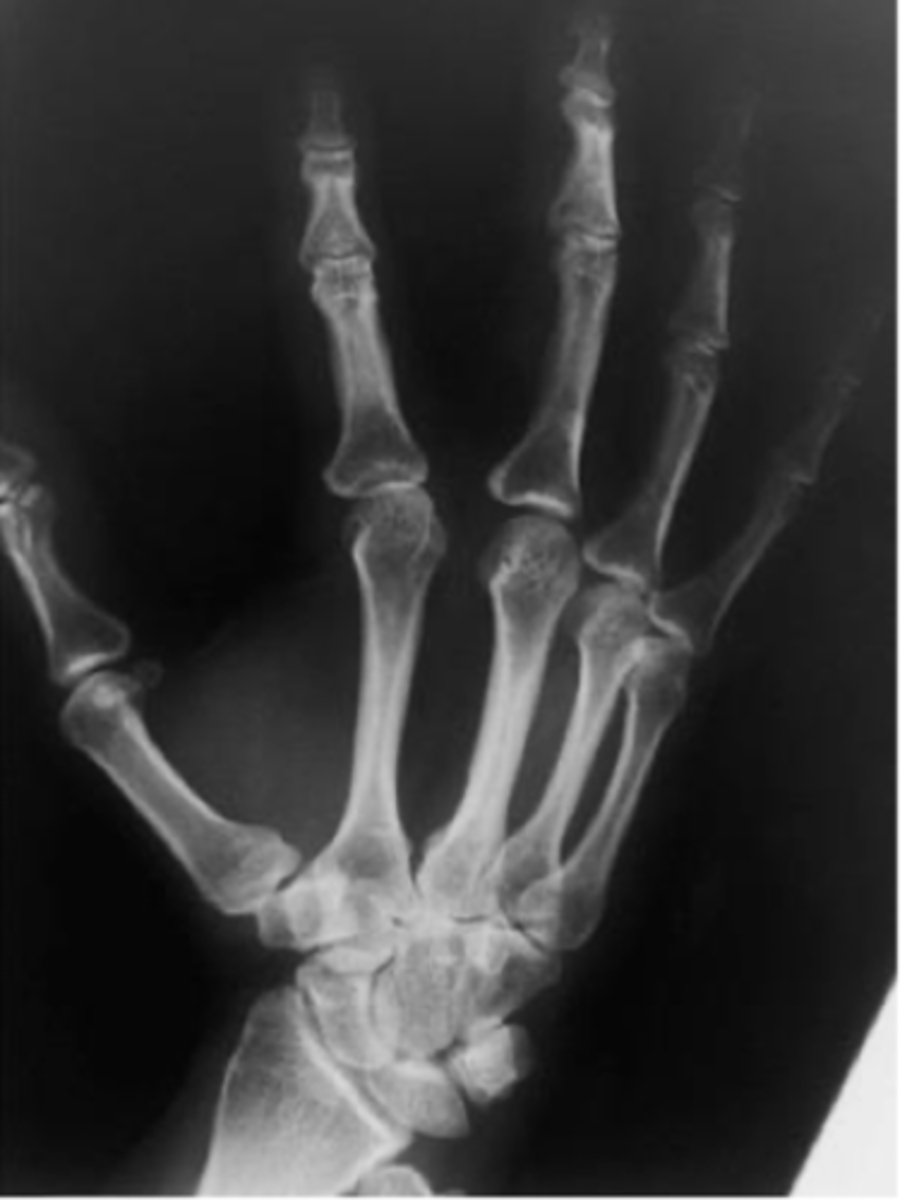

Oblique hand

What view is this?